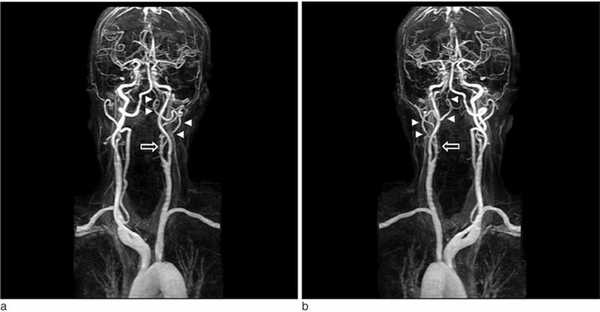

МРА сосудов головы и шеи

МР-ангиография сосудов шеи